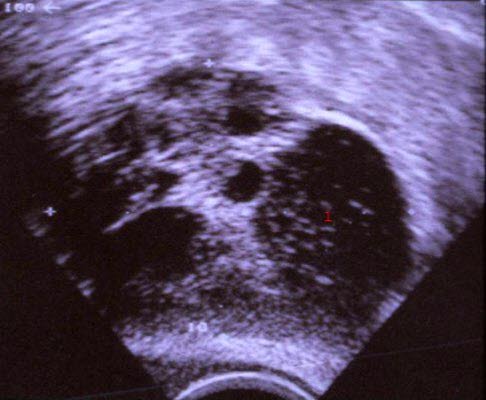

Torbiele wielokomorowe: torbiel tekaluteinowa ziarniniakowa, badanie ultrasonograficzne